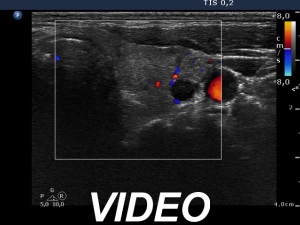

Ultrasonography. The thyroid was echonormal. A large nodular area occupied great part of the right lobe. This area was composed of discrete lesions with different echogenicities. The nodular are presented signs of perinodular blood flow. There were small discrete lesions in the left lobe.

It is worth analyzing the ultrasound presentation. At first sight, a follicular tumor seems very likely: a large solitary nodule with halo sign occupies great proportion of a lobe. However, a more thorough analysis reveals that this large nodular area is composed of discrete lesions; although this feature does not exclude a follicular tumor, it significantly reduces this possibility.